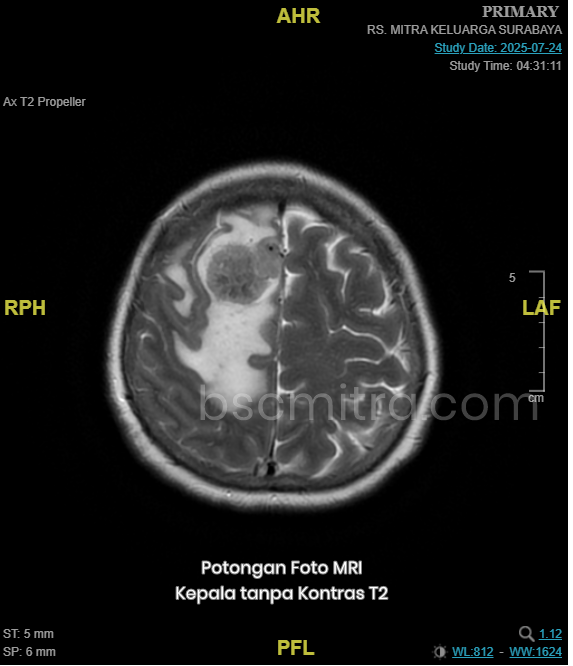

MRI (Magnetic Resonance Imaging) adalah cara pencitraan medis tanpa radiasi untuk menghasilkan gambaran struktur dalam tubuh secara detail, terutama jaringan lunak seperti otak, saraf, dan organ dalam. Pada MRI kepala, berfungsi untuk melihat adanya kelainan yang terjadi pada otak. Baik itu tumor otak, infeksi otak, keadaan otak paska stroke, dsb.

Terdapat dua jenis utama MRI, yaitu MRI kontras dan MRI non-kontras. Keduanya memiliki fungsi dan kegunaan masing-masing, tergantung kondisi yang ingin dideteksi dokter.

Tiap MRI mempunya beberapa sequence foto, seperti T1, T2, Fat Sat dan sebagainya.